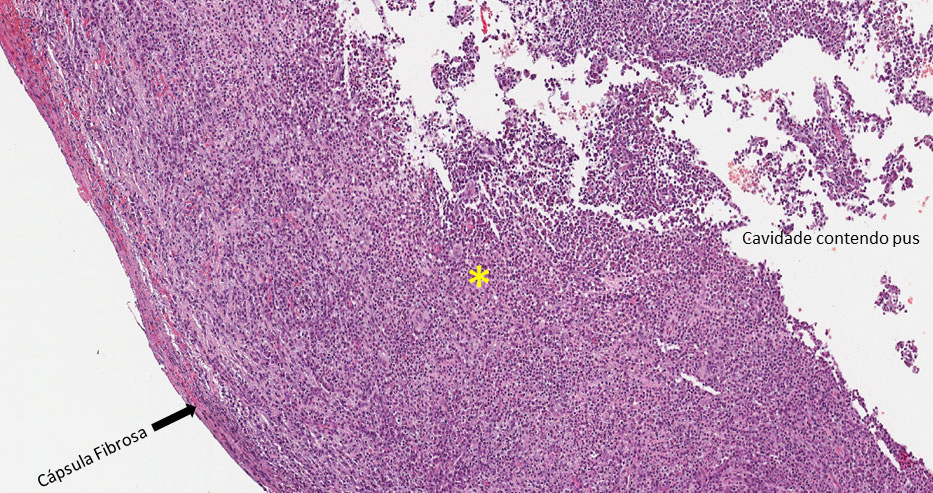

O abcesso apical crônico é caracterizado por uma coleção de pus em uma cavidade não pré-formada, contornado por tecido de granulação e cápsula fibrosa.

Cavidade (lúmen) contendo piócitos (pus), tecido conjuntivo contendo neutrófilos, infiltrado inflamatório linfoplasmocitário (asterisco amarelo) e vasos de neoformação, externamente cápsula fibrosa, caracterizando tecido de granulação. (Figura 1)

Observar a cavidade virtual, contendo pus (piócitos — Figura 2 — área tracejada em preto e setas), circundada por tecido de granulação apresentando infiltrado inflamatório contendo plasmócitos (asterisco amarelo-Figura 3) linfócitos (asterisco verde), neoformação vascular e fibroplasia (seta A — Figura 3). Na periferia observa-se uma maior deposição de fibras colágenas caracterizando uma cápsula fibrosa.

Abscesso Apical Crônico